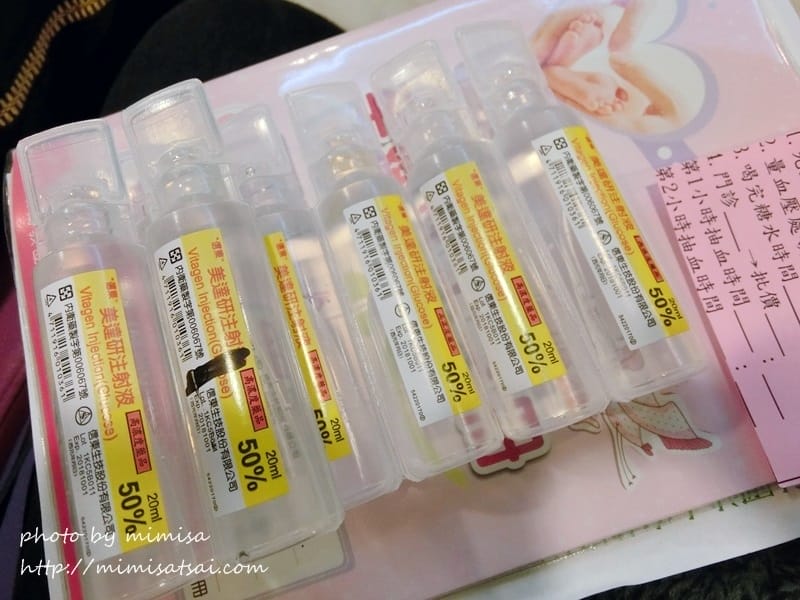

然後我從26W後的產檢就開始把測宮縮頻率當作例行檢查了

因為從開始懷孕的產檢醫生每次必說一句話,就是:你的肚子很緊很繃唷!!!

所以到後期就把宮縮頻率當作例行檢查啦!!!

但還好是測出來也都沒什麼問題